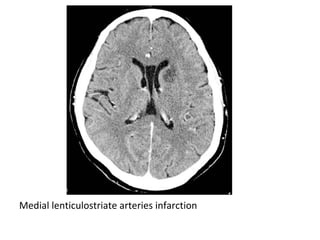

Medial lenticulostriate arteries infarction